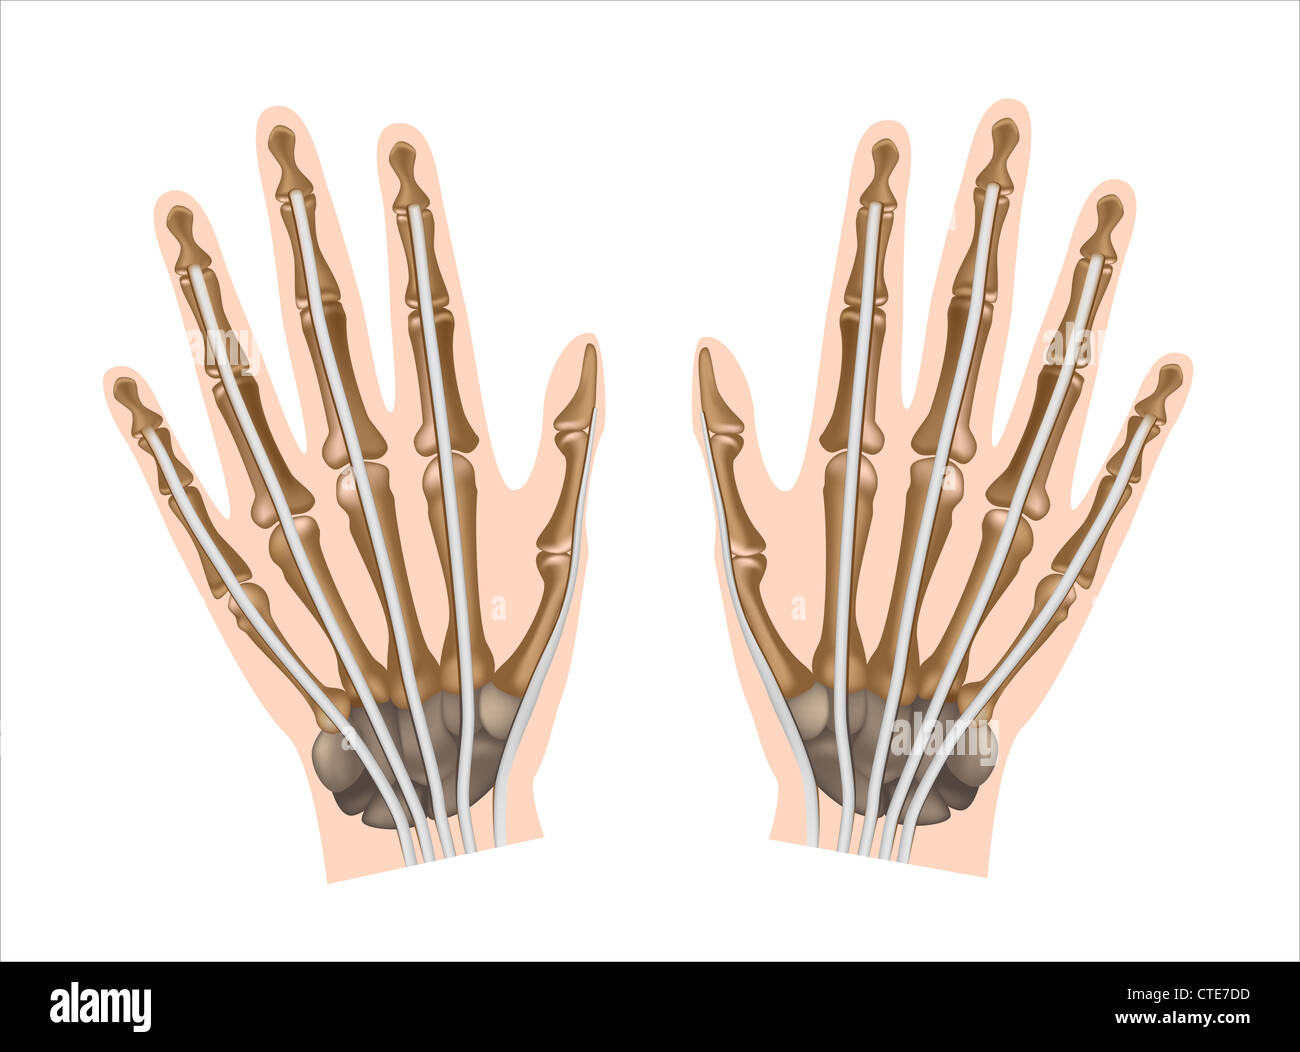

Tendones de la mano ligamentos de la mano Imágenes de stock en blanco y negro Alamy